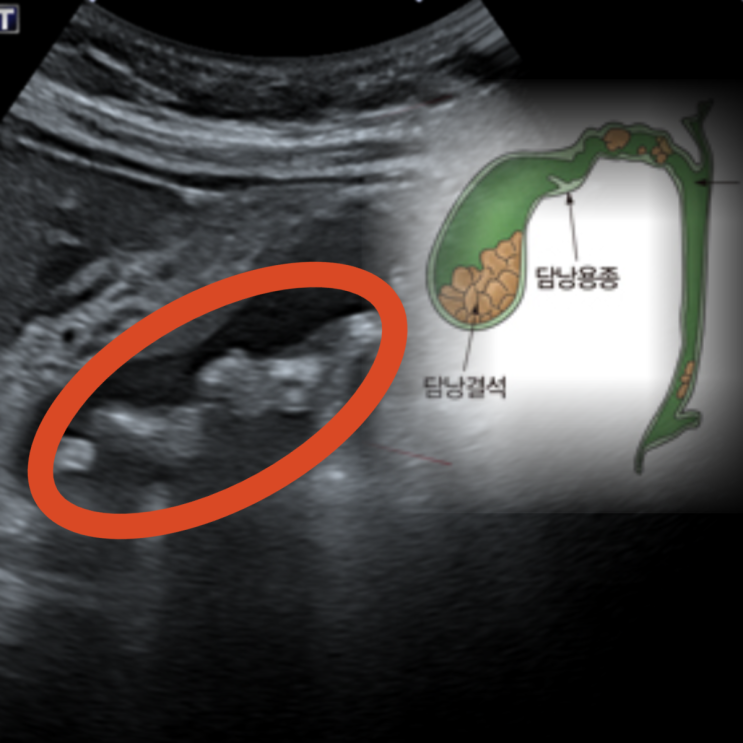

1. 담석증 & 담낭염

기름진 음식 후 우상복부 통증, 등이나 어깨로 방사, 구역구토가 흔하며, 염증이 생기면 고열심한 통증복부 압통이 동반됩니다.